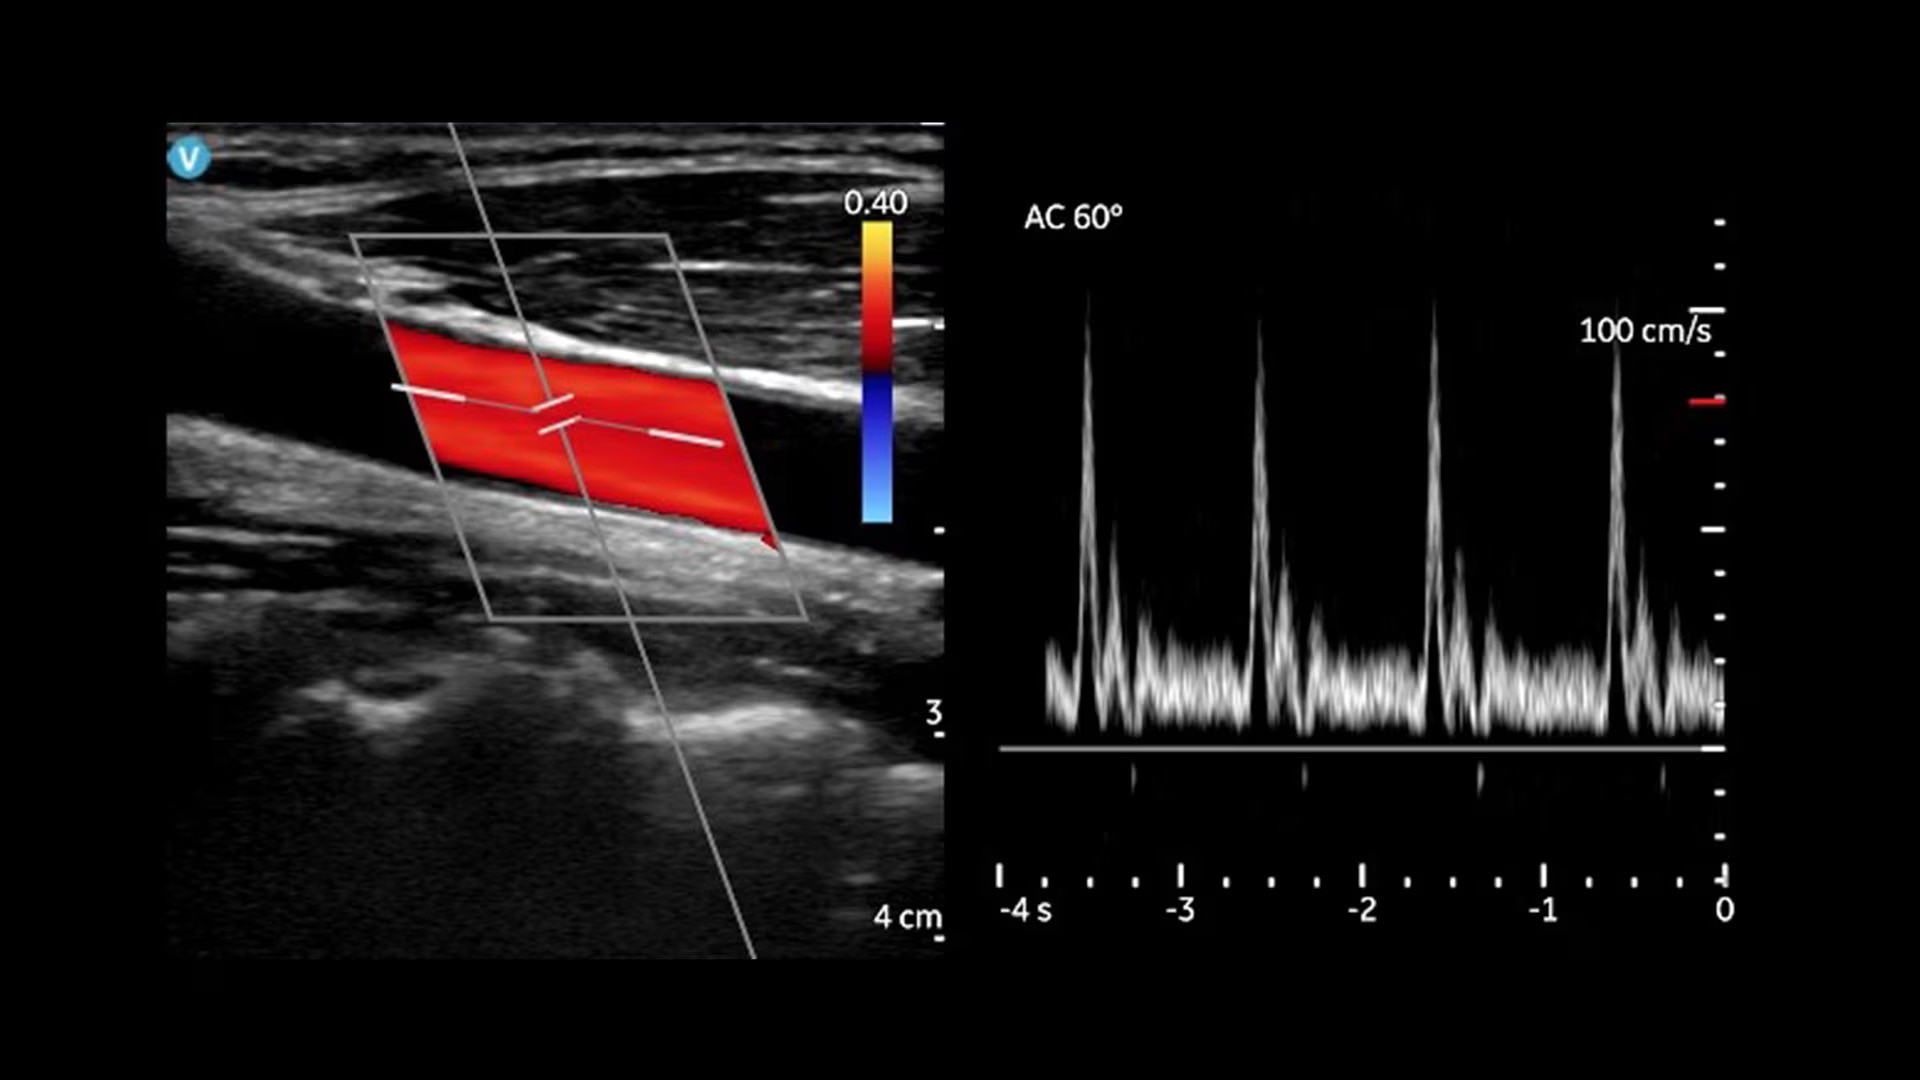

Vscan Air CL offers curved array and linear array transducers in a dual-probe configuration. The curved transducer is ideal for abdominal imaging, obstetric assessments and more, and the linear array is ideal for vascular, MSK, lungs and more. Complete both shallow and deep scans with one device without compromising image quality.

Linear array: Peripheral Vascular, Lung/Thoracic (Adult /Pediatric), Small organs (Adult/Pediatric), Musculoskeletal — (Superficial and conventional) (Adult/Pediatrics), Nerves (Adult/Pediatrics), Neck and airway (Adult /Pediatric), Procedural guidance (Adult/Pediatrics), Ophthalmic*, Cephalic (Neonatal).